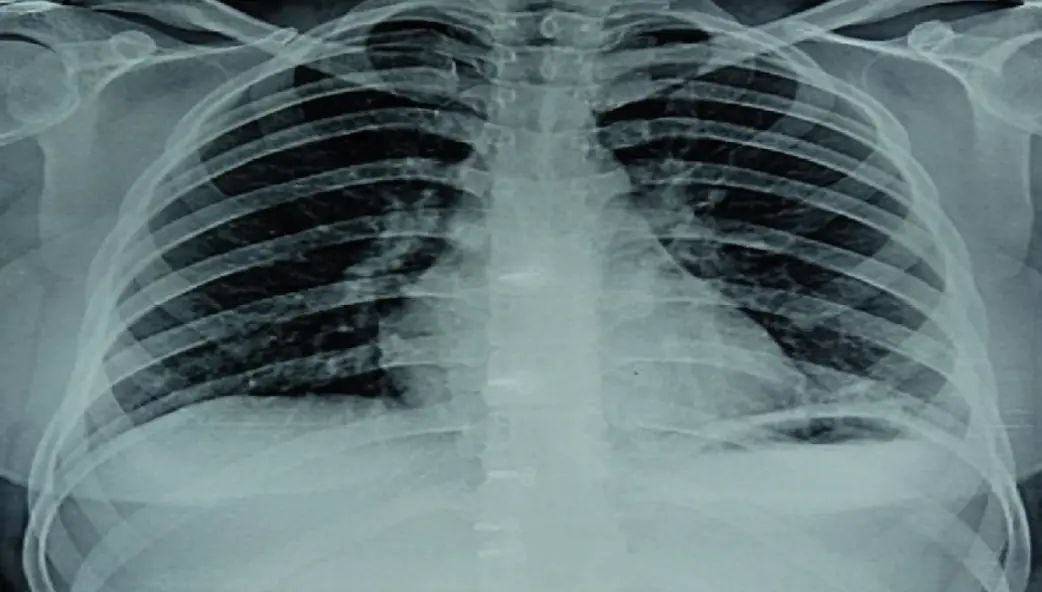

Hydrocarbons (Inhaled/Ingested)

- Agents: Kerosene, gasoline, lighter fluid.

- Pathophysiology: Low surface tension → aspiration pneumonitis.

- Clinical: Coughing, choking, hypoxia.

- X-Ray Finding: Pneumonitis (often within hours), usually in the lower lobes.